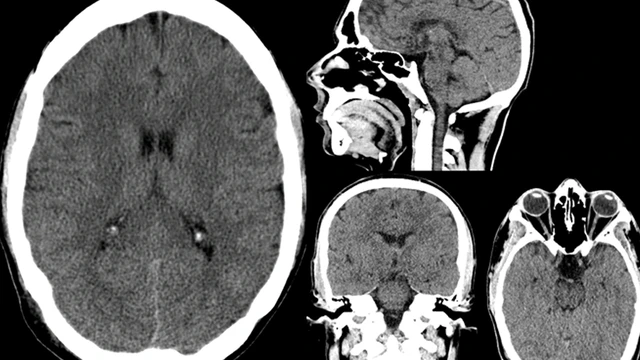

não thế nào? Chụp CT não là một trong những kỹ thuật chẩn đoán hình ảnh quan trọng, thường được chỉ định trong các trường hợp nghi ngờ chấn thương sọ não, đột quỵ, u não, viêm não hay các bất thường thần kinh khác. Tuy nhiên, bên cạnh mối quan tâm về chỉ định và quy trình thực hiện, nhiều người vẫn băn khoăn không biết chụp CT não giá bao nhiêu?

Chụp CT sọ não là kỹ thuật chẩn đoán cận lâm sàng giúp bác sĩ phát hiện các bất thường ở vùng đầu và mặt. Kết quả chụp CT cung cấp hình ảnh chi tiết, cho phép bác sĩ xác định nguyên nhân gây bệnh, vị trí tổn thương và đề xuất phương pháp điều trị phù hợp. Đây là công cụ quan trọng hỗ trợ chẩn đoán nhanh chóng và chính xác trong các tình huống khẩn cấp hoặc khi cần đánh giá tổn thương não bộ.